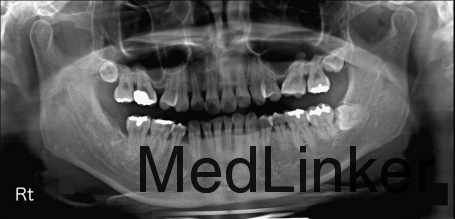

凸面型,骨性II类,青少年期拔除了3颗前磨牙但由于其他原因未继续矫正,深覆合,覆盖5.5mm,右侧磨牙I类,左侧磨牙II类关系,双侧尖牙II类

诊断:骨性II类,安氏II类,牙列间隙 治疗:上颌先上.022直丝拖槽,14niti排齐整平,依次换丝,为打开前牙咬合,16*22TMA弯制压低辅弓,如图。打开咬合后,粘接下颌拖槽,继续矫正。